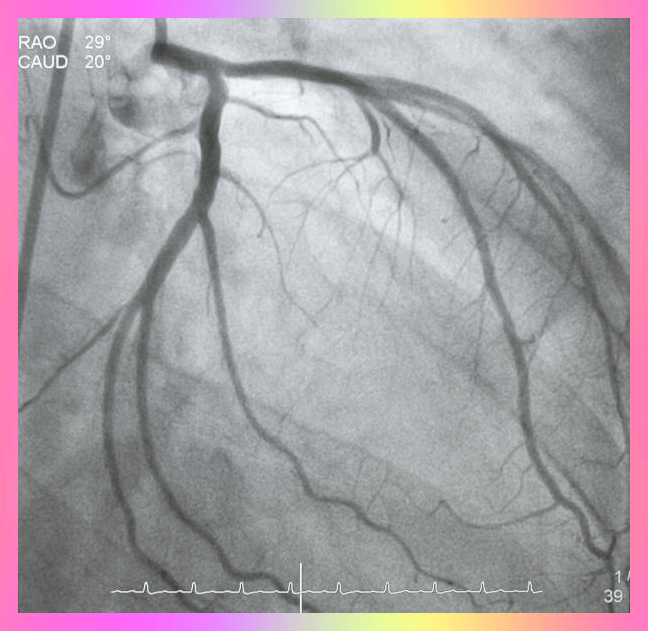

협심증은 그 자체로 질병이 아니지만 일반적으로 관상 동맥 심장 질환과 같은 심장 문제의 증상으로 심장근육이 혈액에서 충분한 산소를 얻지 못할 때 생기는 것으로 가슴 통증이나 압박감을 느끼게 되며 주변에 있는 팔, 어깨, 목, 등 또는 턱까지도 증상이 전파된다고 합니다.

협심증 검사가 필요한 경우 진단 테스트를 하면 되는데요 아래와 같은 방법이 있습니다. 그래서 가슴 답답하고 팔과 턱으로 퍼지는 묵직한 통증이 느껴지고 식은땀이 나는 경우는 바로 병원 직을 해서 아래 검사를 받아야 합니다.

- 혈액 검사

- 흉부 엑스레이

- 심전도 (EKG)

- 스트레스 테스트

치료는 원인에 따라 다르며, 약물 치료, 생활 습관 변화 및 심장 시술도 한다고 합니다.